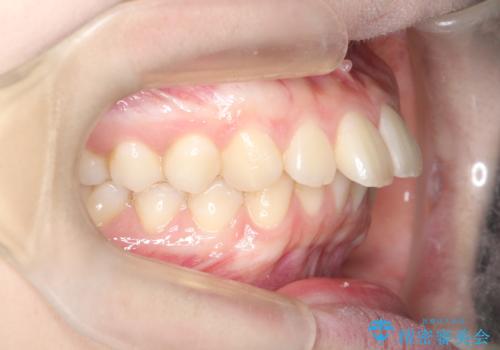

上と下の前歯がずれているため、抜歯を行い前歯の真ん中を合わせる治療計画を立ててワイヤー矯正にて治療を行いました。

2年という矯正期間でしたが、かみ合わせも良くなりを患者様には満足していただくことができました。